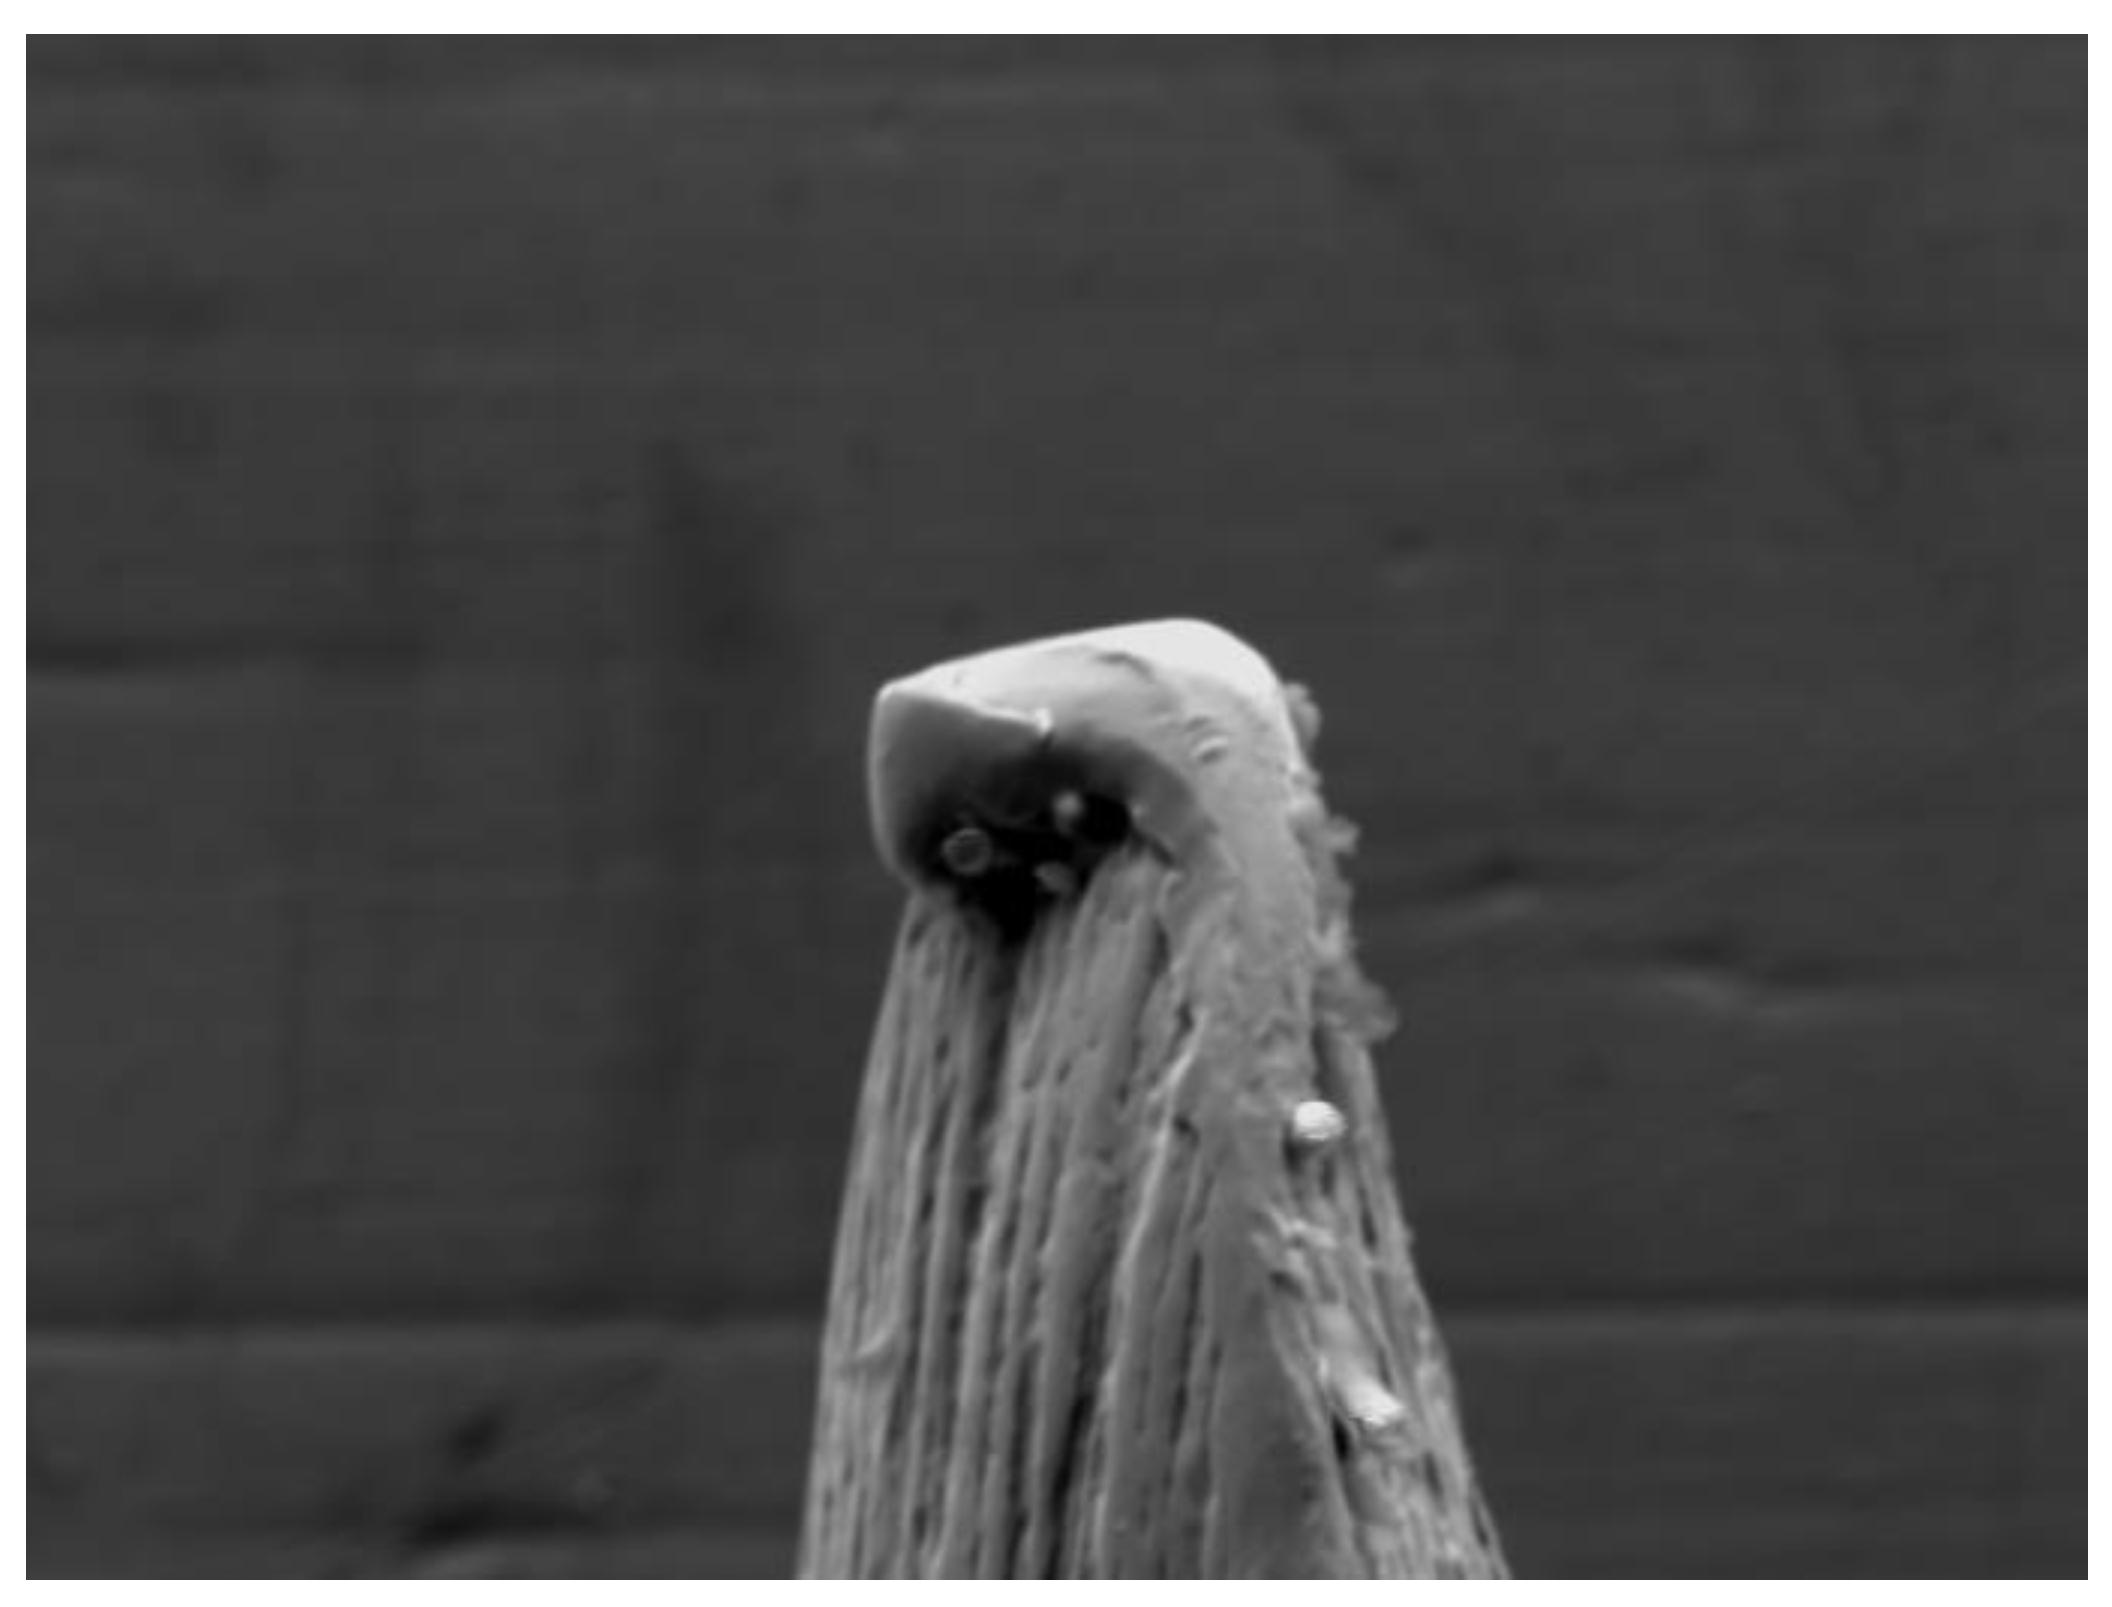

This delicate part of the needle, because of its shape and the thin thicknesses, is susceptible to deformation after use, especially if repeated, with the appearance of barbs or irregularities which can both limit its ability to penetrate in soft tissues and induce micro-traumas in the areas where the anesthetic is injected [14] (Figure 3).

It is important to underline that the deformations were all observed in the tip of the bevel where the wall thicknesses are more reduced and make the tip of the needle most susceptible to deforming (Figure 11 and Figure 12).

Figure 3. Deformation of the needle tip observed under SEM.

Preprints 111024 g003